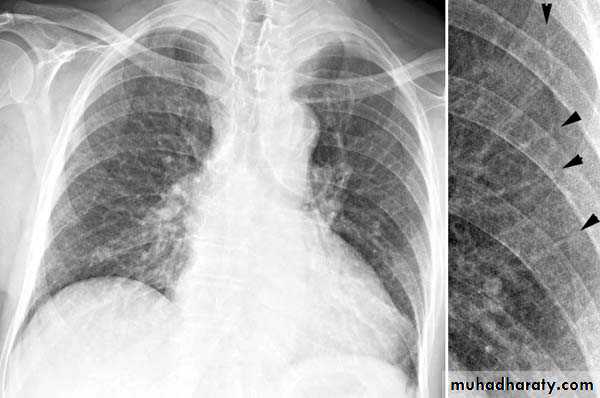

Right upper lobe consolidation

RUL consolidation will be seen as an increased opacity within the right upper lobe. Opacity may be sharply bordered by the horizontal fissureSome loss of outline of the upper right heart border may be apparent

Radiological sign in chest radiograph

Dense opacity seen above the horizontal fissure.

Air-bronchogram line

The lower border of the consolidation is sharply delinated by the horizontal fissure suggesting it lies in the anterior segment of the RUL